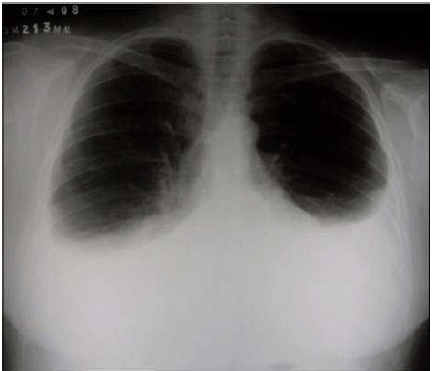

Paciente com diagnóstico prévio de Insuficiência Cardíaca Congestiva, internado no Pronto Atendimento de um Hospital público, queixa-se de piora do quadro nas últimas 12 horas. Apresenta dispneia, esforço respiratório, desconforto torácico, murmúrio vesicular abolido nas porções inferiores dos pulmões, FTV abolido com macicez a percussão. Realizado Rx de tórax mostrado na figura abaixo.

O quadro clínico e radiológico sugerem qual provável evolução da Insuficiência Cardíaca?